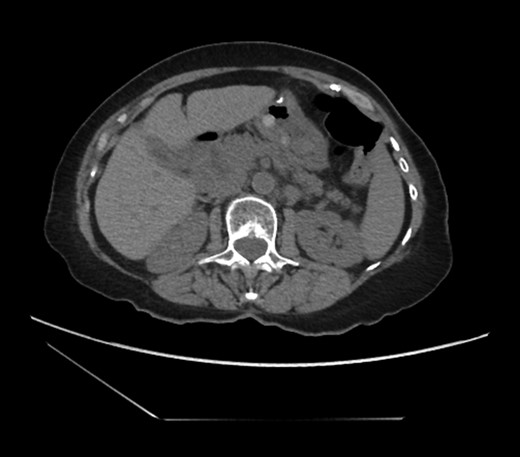

An 81-year-old female with a medical history of CAD with stents, hyperlipidemia, hypothyroidism, GERD, recent UTI, pancreatic cyst, constipation, anemia and leukopenia presented to the ED with a 1 day history of mild, diffuse and cramping abdominal pain. The patient was unable to give an accurate history, but the son at bedside supplemented this reporting that for several years the patient had been experiencing ill-defined abdominal discomfort. Physical exam showed a soft abdomen with mild tenderness and no evidence of peritonitis. A CT scan of the abdomen and pelvis with IV and PO contrast (Fig. 1) showed edematous changes to the mesentery of the small and large bowel with swirling of vessels indicative of internal hernia. The stomach was also noted to be distended with both air and fluid as a consequence of posterior compression by the hernia contents (Fig. 2). A surgical consult was obtained, a nasogastric tube and Foley catheter were placed, antibiotics were started, and the patient was taken for an exploratory laparotomy. Upon entering the abdomen through a vertical midline incision, 1.5 l of ascites was drained revealing a diffusely edematous mesentery. A large portion of the small bowel was seen to be herniated through the Foramen of Winslow (Fig. 3). A Kocher maneuver and division of the gastrocolic ligament were then performed to allow release of the herniated small bowel. It was at this time that, in addition to small bowel, a large portion of the ascending and transverse colon was noted to be herniated through the foramen of Winslow. The small bowel was also seen to be torsed about its own mesentery. Normal anatomy was restored and the bowel noted to be healthy and viable with peristalsis (Fig. 4). Due to the large size of the foramen after reduction and enlargement, it was deemed best to leave it open to prevent any further incarceration or strangulation. The abdomen was closed and the patient tolerated the procedure well. At a follow-up visit 2 months later, the patient had well-healed incisions, was doing well, tolerating a diet, and gaining weight appropriately.

Externalized abdominal contents shown to be pink and healthy bowel with some areas of ecchymosis in the transverse colon.